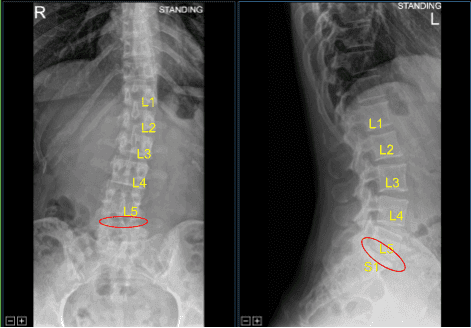

The patient presented to the neurosurgery clinic with signs and symptoms of lumbar spondylosis and radiculopathy at L5-S1 level of their lumbosacral spine. They failed extensive conservative measures and surgery is recommended to decompress and stabilize their lumbar spine.

Moderate Disc Degeneration